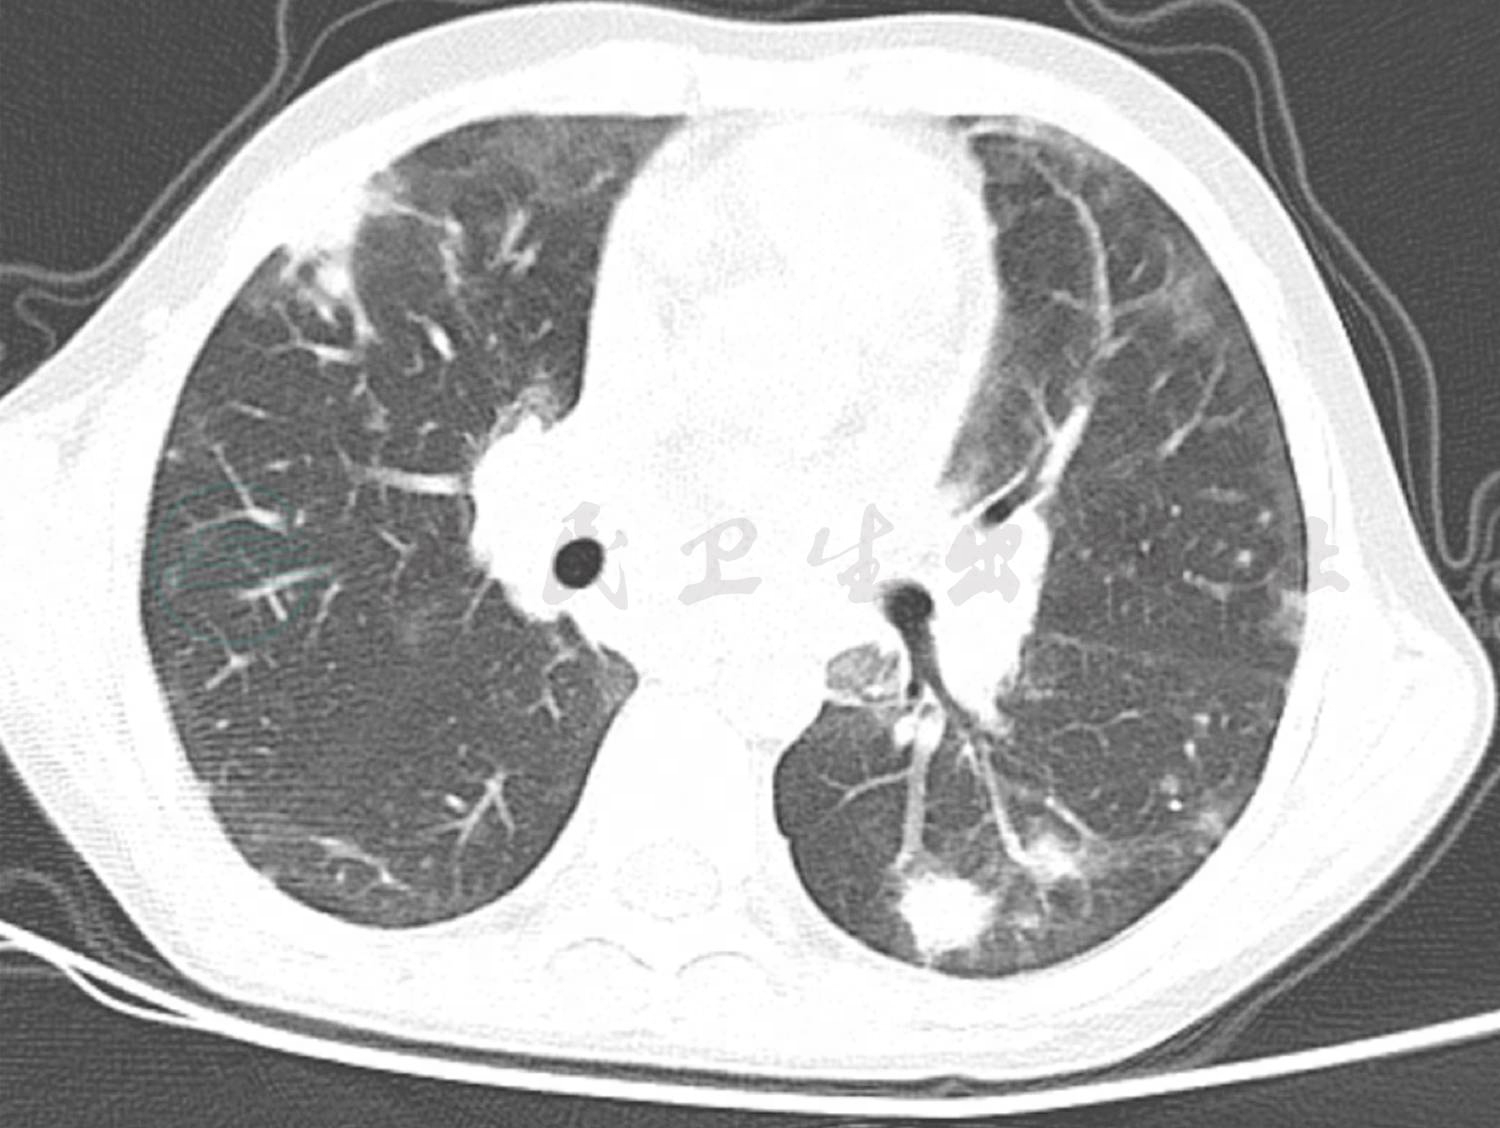

患儿入院1周后复查肺CT(图2),提示双肺多发结节影,部分结节贴近胸膜,考虑不除外真菌感染,予氟康唑治疗1周后复查肺CT(图3)提示双肺结节影较前增多、增大,将氟康唑换为伏立康唑治疗9天,因患儿肺部持续有结节影,此次复查肺部增强CT(图4),双肺结节影较前无明显变化,增强扫描时明显强化。此时患儿出现了反复发热,我们先后加用亚胺培南及万古霉素治疗后患儿体温逐渐平稳。患儿肺部病变经过高级抗生素及抗真菌药物治疗,并无明显好转,且治疗中仍有发热,因此,我们再次考虑患儿可能存在免疫缺陷,因此,予患儿进行免疫缺陷相关基因检测。最终,基因检测结果提示患儿为普通变异性免疫缺陷症8型伴自身免疫,此病是一种常染色体隐性遗传免疫缺陷,伴随B细胞分化缺陷和抗体产生减少或缺失。临床表现为免疫缺陷,复发性感染,低丙种球蛋白血症,特异性抗体应答缺失,自身免疫性溶血性贫血,血小板减少性紫癜,炎性肠病。由此可以解释患儿顽固性血小板减少。

图2A 4月5日肺CT:双肺间质性改变较前无明显改善

图2B 4月5日肺CT:双肺多发结节影,部分结节贴近胸膜

图3 4月11日肺CT:双肺结节影较前增多、增大

图4 4月20日肺CT:双肺结节影较前无明显变化,增强时明显强化